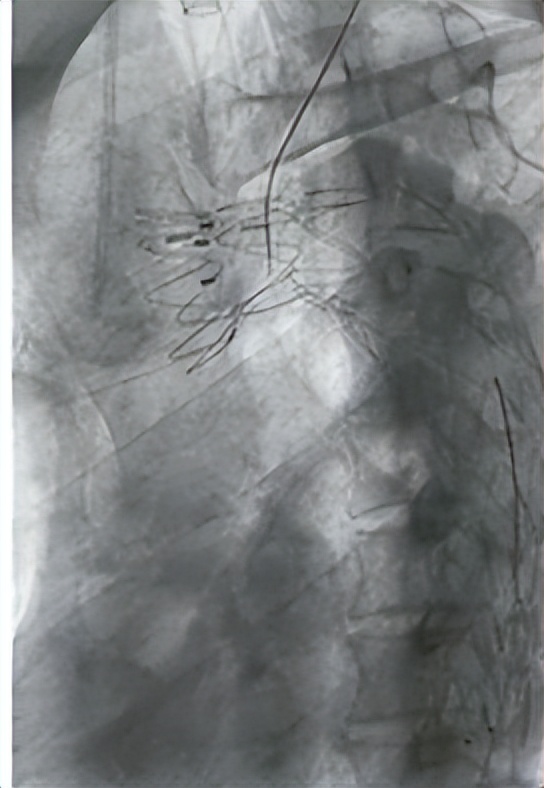

术中穿刺针通过左锁骨下动脉刺透胸主动脉内的覆膜支架

术后造影显示主动脉动脉及左锁骨下动脉内覆膜支架重塑血管腔